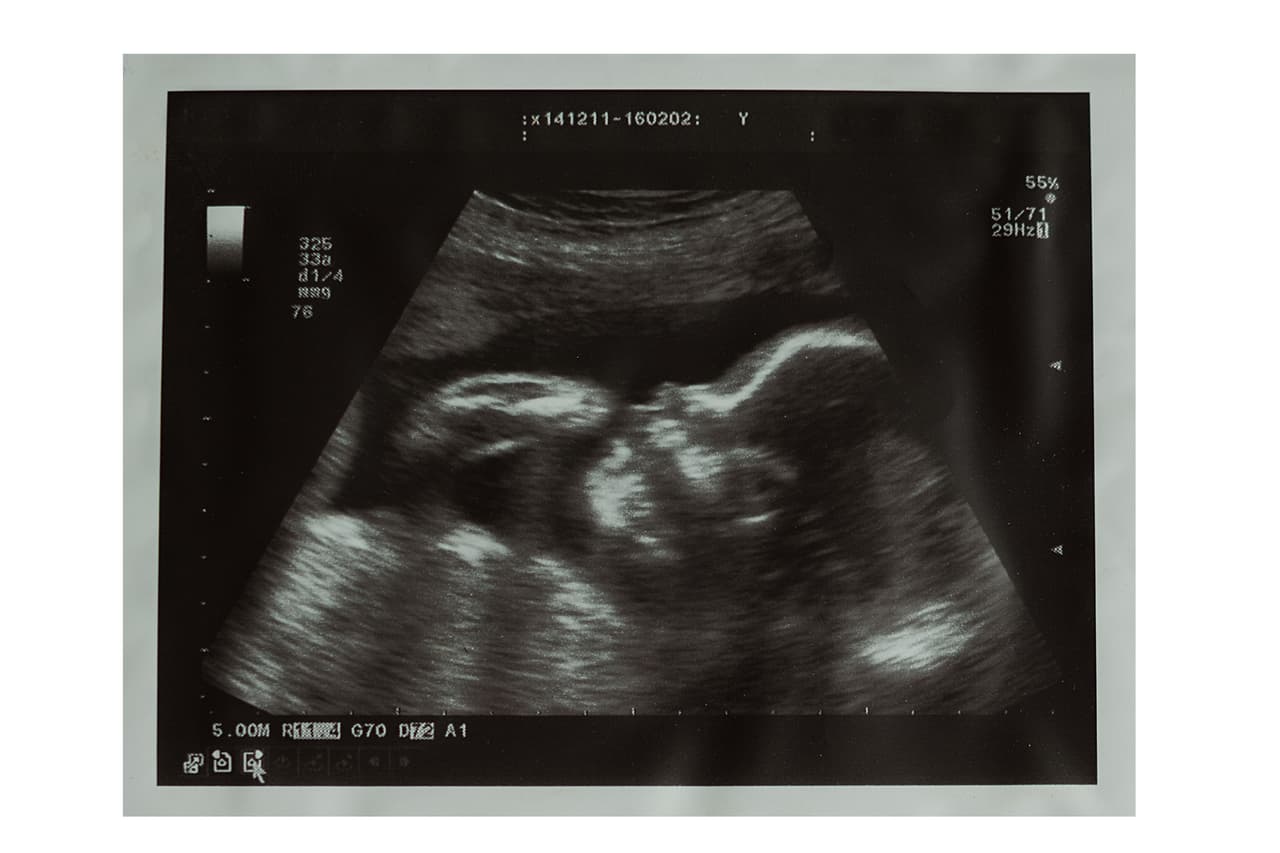

Si una mujer está en el tercer trimestre y ha sido infectada con zika, en cada visita nos centramos en la planificación del nacimiento, en monitorear al bebé mediante las ecografías y en revisar juntas las últimas investigaciones sobre el tema.

También podemos planear ecosonogramas mensuales. Es posible que un bebé que parece normal en un ultrasonido muestre problemas en otro realizado más adelante. Algunos problemas se pueden desarrollar con el tiempo y volverse evidentes luego. Sin embargo, los ultrasonidos no pueden detectar todos los problemas y la microcefalia no es el único problema que puede causar el zika. Por lo tanto, planeamos el parto en un hospital con pediatras que sepan de zika y que puedan prepararse para el cuidado de los recién nacidos. Revisamos con cuidado los ojos y los oídos del bebé y en algunos casos realizamos radiografías del cerebro después del nacimiento.